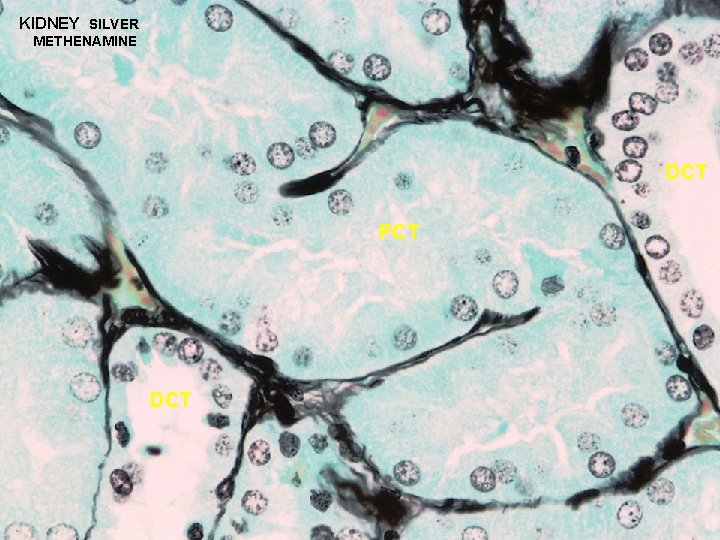

URINARY SYSTEM CORTEX: CORTICAL LABYRINTH 1 - RENAL CORPUSCLES 2 - PROXIMAL CONVOLUTED TUBULES - longer than DCT and thus more numerous - stain slightly darker and have a larger diameter than DCT - cells are larger and have an irregular luminal surface due to the presence of a “brush border” and glycocalyx 3 - DISTAL CONVOLUTED TUBULES - shorter than PCT and thus less prevalent - stain slightly lighter and have a smaller diameter than PCT - cells are smaller and cuboidal, thus more nuclei are apparent in a cross section of a DCT - luminal surface is more uniform since it lacks a brush border

KIDNEY SILVER METHENAMINE DCT PCT DCT